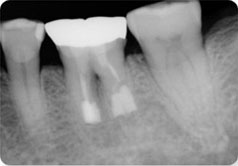

뿌리 끝에 염증이 생겼으나 치근단절제술을 할 수 없는 경우

의도적 재식술로 치아를 살릴 수 있는 경우

뿌리끝에 염증이 생겨 옆으로 튀어나온 모습입니다. 재식술에 의해 치료 후 원래의 치아를 계속 사용합니다.